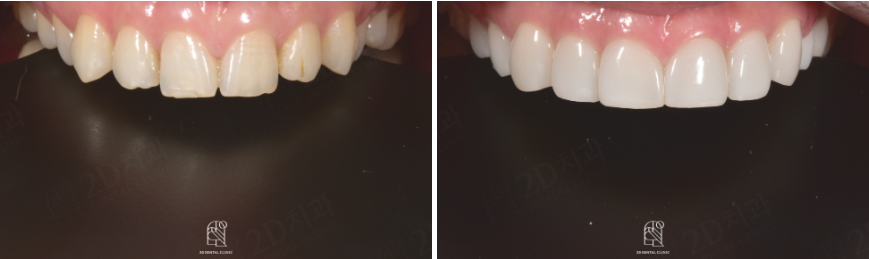

BEFORE

AFTER

앞니가 깨졌다면 꼼꼼한 상담을 통해서

그에 맞는 치료방법을 선택해야합니다.

앞니는 음식물을 절단하는 역할을 하고 얼굴의 정면에 위치한 치아인 앞니가 치아깨짐이 가장많이 발생하는데요. 치아가 깨진 경우에는 깨진 정도에 따라 치료방법이 달라지는데 깨짐이 작은 경우에는 비교적 간단히 치료가 가능하고 파손범위가 넓고 신경손상까지 의심된다면 엑스레이 촬영을 통해 치아 뿌리에 이상이 있는지 확인해야합니다.